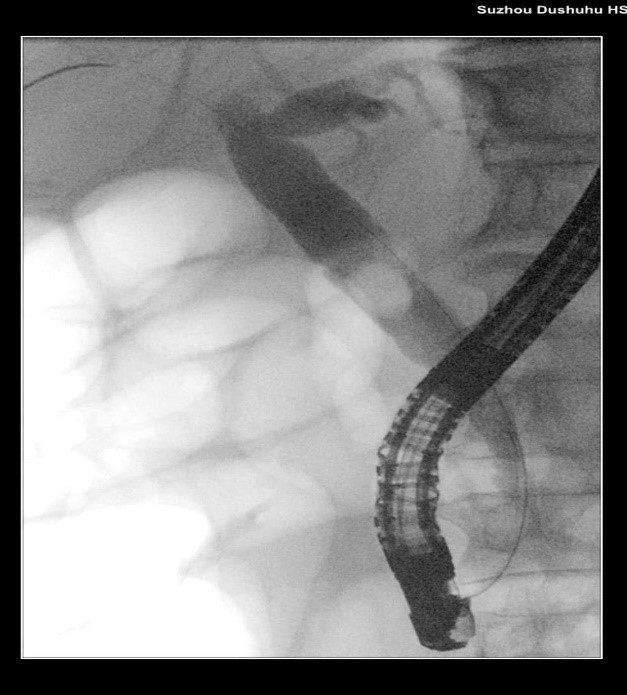

苏大附四院ERCP团队在手术中看到陈大爷的胆总管在结石的影响下已经宽达13mm,结石大小11*10mm,将十二指肠乳头切开并扩张后用取石球囊把结石取出,置入胆管支架使胆汁充分引流,顺利解除了胆道梗阻。

扩张取石

取石前后